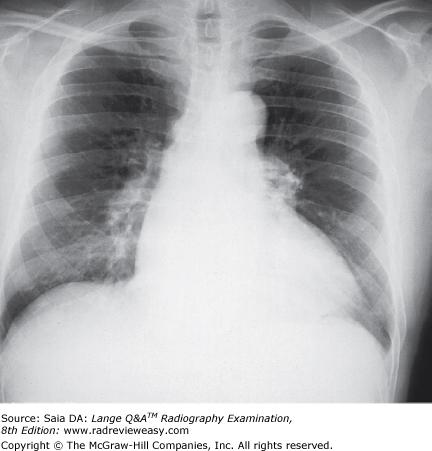

Which of the following criteria are used to evaluate a PA projection of the chest?

D 1, 2, and 3

-To evaluate sufficient inspiration and lung expansion, 10 posterior ribs should be visualized. The sternoclavicular joints should be symmetrical; any loss of symmetry indicates rotation. To visualize maximum lung area, the shoulders are rolled forward to move the scapulae laterally from the lung fields.